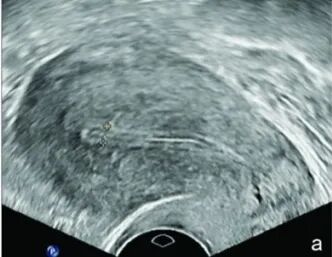

子宫内膜形态就是附着在宫腔上的柔软光滑的黏膜组织,可以粗糙理解为宝宝住的房子内部装修是否平整,越平整胎儿就越喜欢住在里面。

在超声里,指在阴道B超下子宫内膜与子宫肌层的相会回声,根据Gonen标准可分为三种类型:

A型:可监测到典型的三线征或多层子宫内膜;

C型:均质强回声,无内膜中线回声。

如果你拿到B超片子以后,发现自己属于A型,那就要恭喜你了。因为A型内膜相较于B、C型,胚胎的植入率和临床妊娠率都比较高,是适合胚胎植入的最佳内膜形态。